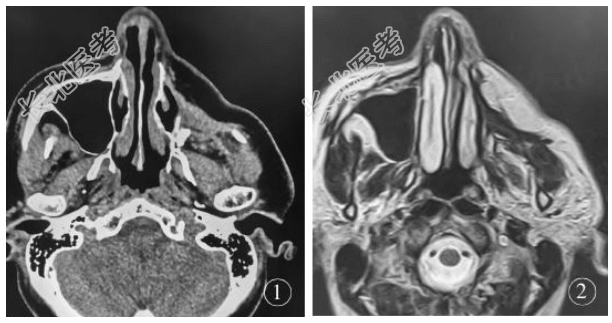

专科检查:双侧面颊部不对称,左侧颌面部软组织明显凹陷约2.0cm×3.0cm×5.0cm。皮肤软组织与颌面骨骨质明显粘连,皮肤软组织活动性较差,左侧颌面部肌肉活动时,其表面皮肤可见明显牵拉,张口功能未见明显受限。头部CT平扫(图1)显示:左侧上颌窦骨壁及部分颧骨缺如,未显示正常上颌窦结构,双侧颌面部不对称,左侧颌面部凹陷。头部MRI(图2)显示:双侧颌面部不对称,左侧颌面部凹陷,左侧颌面部皮下脂肪层覆盖于左侧颞肌前外侧,左侧无正常上颌窦结构。入院诊断:左侧面部凹陷畸形。